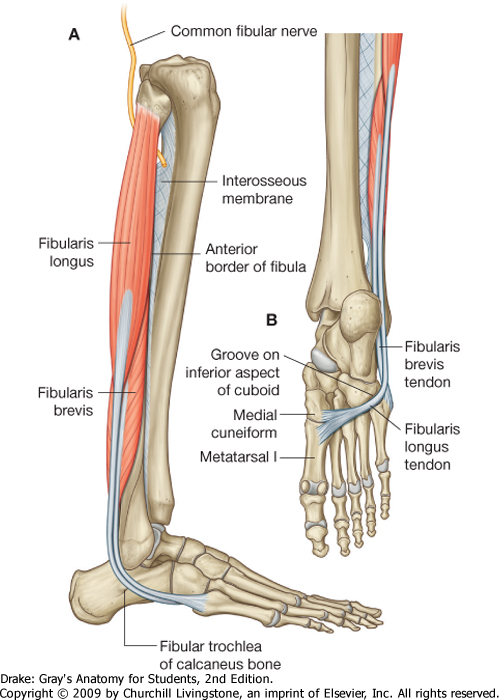

common fibular n. 傳到 Fibularis longus下再分支

flowchart TB si[Siatic nerve] p((popliteal)) cf[Common fibular] si-->p-->cf cf-->lsc[lat. sural cutaneous n.] cf-->sf[Superficial fibular n.] sf-->mc[medial dorsal cutaneous br.] sf-->ic[intermediate dorsal cutaneous br.] cf-->df[Deep fibular n.]

Muscle